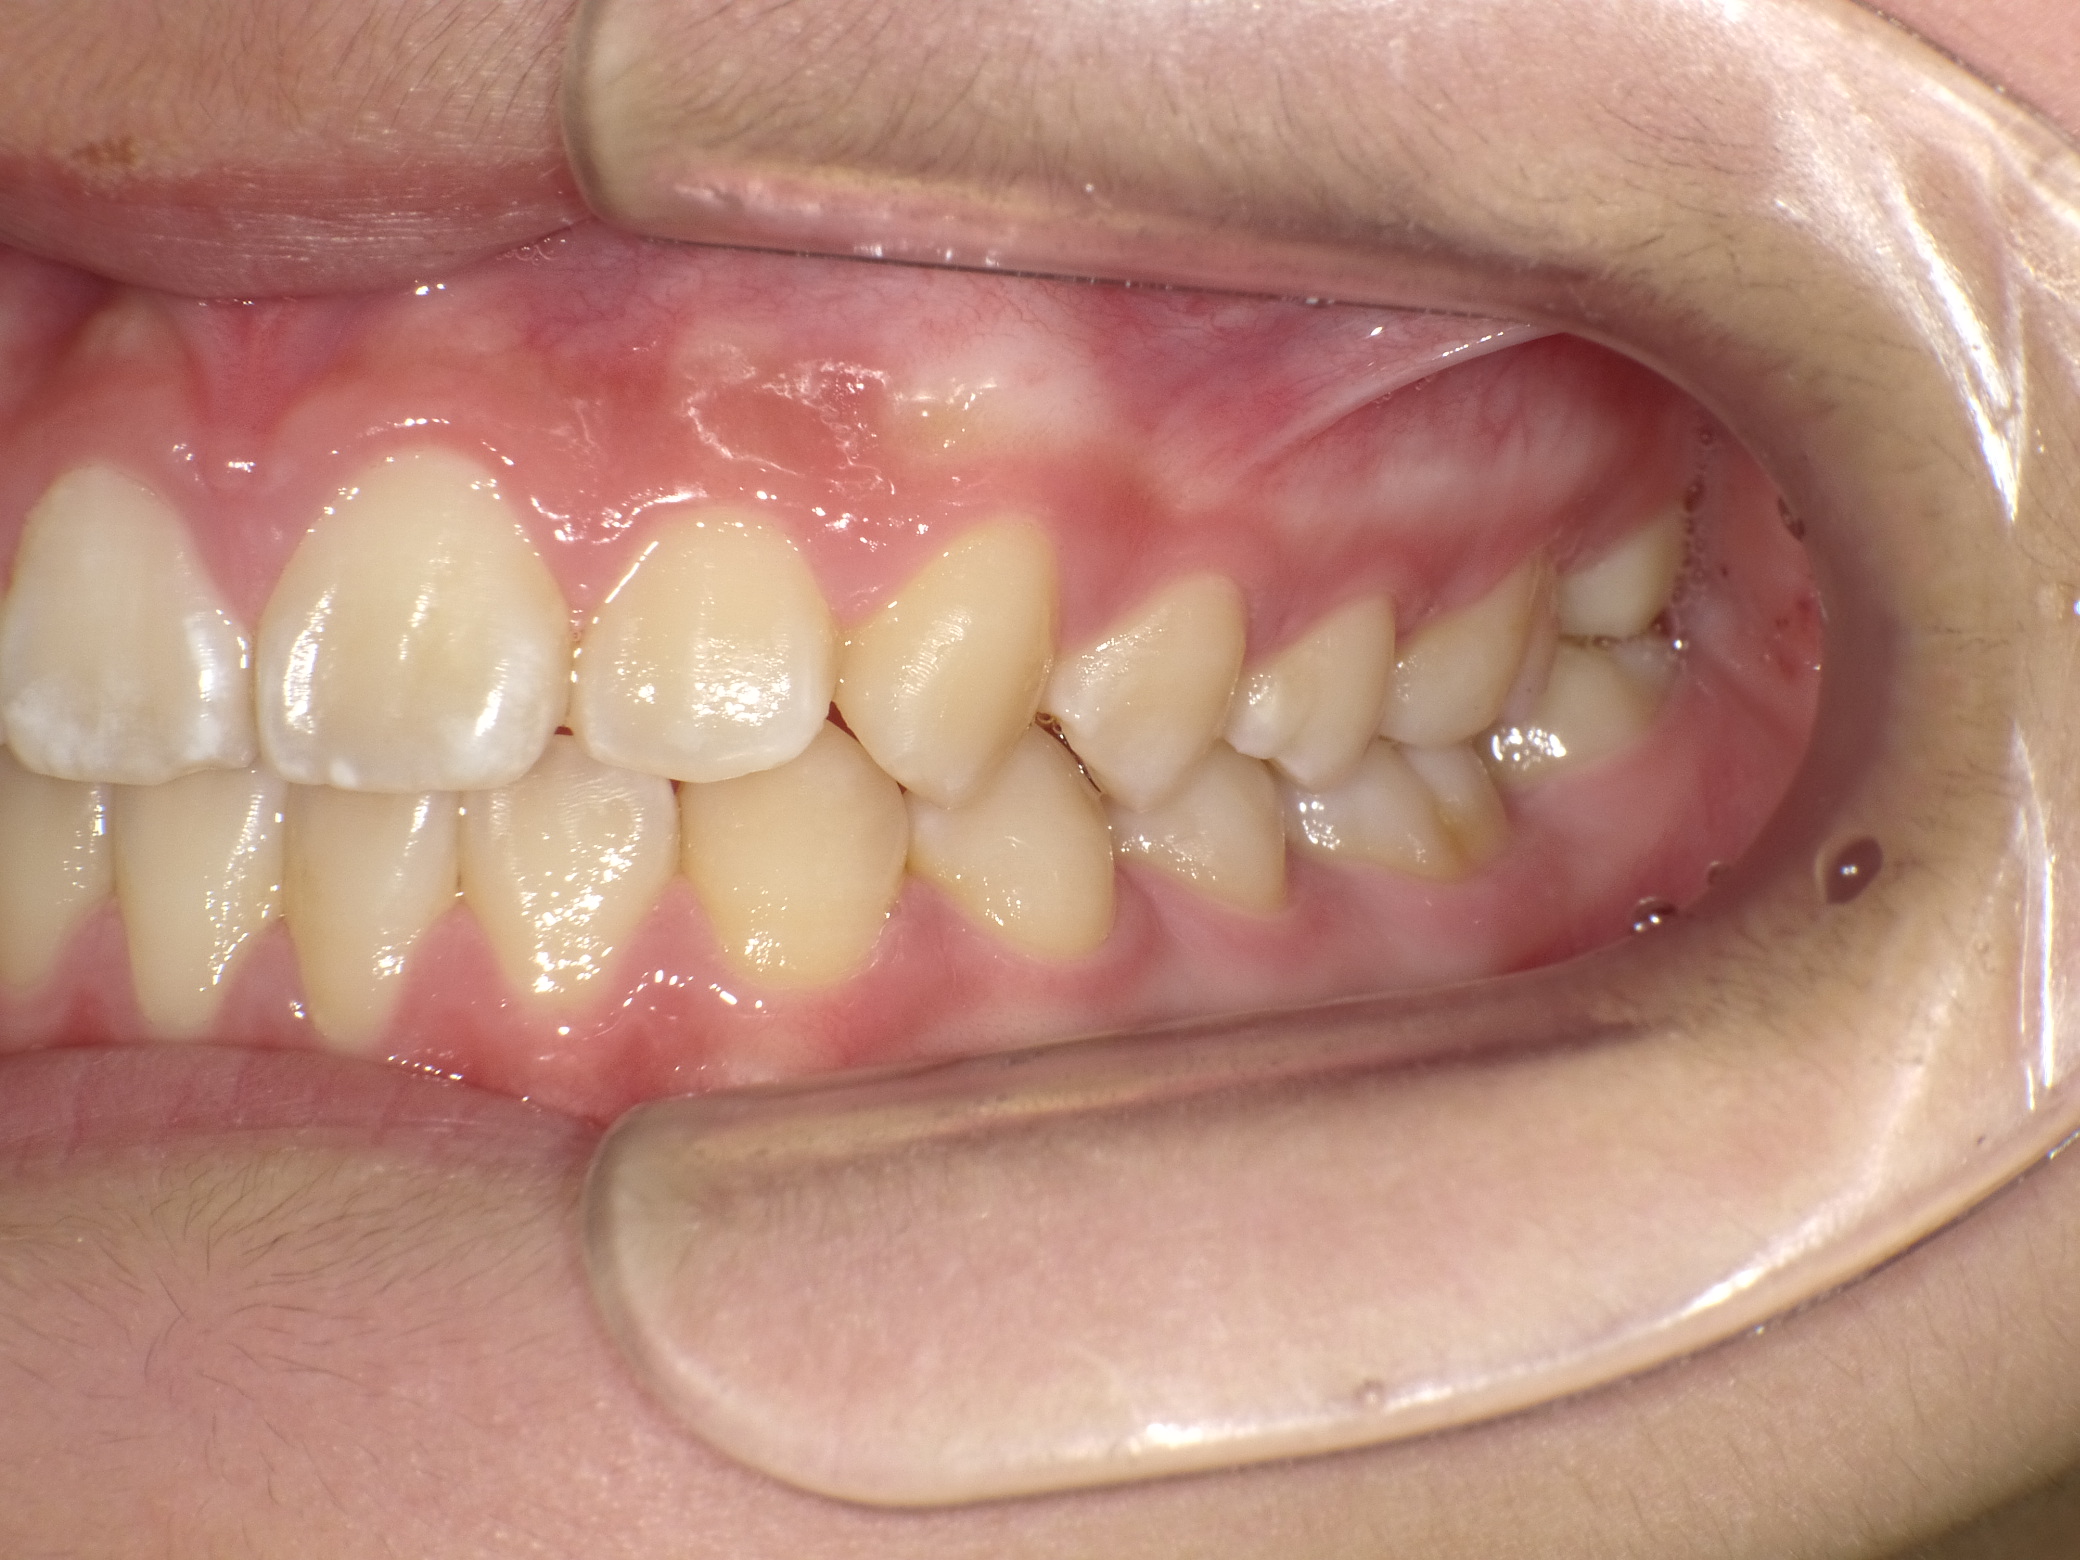

【小学生】マイオブレース矯正 受け口を改善 ③

小学生で開始

マイオブレース

受け口

非抜歯

1期治療のみで改善

Before

After

治療期間

2.3年

治療開始

10歳

種類

マイオブレース矯正

使用装置

機能矯正装置 上顎前方けん引装置

コメント

現在は治療終了後10年程経っています。

今では とても綺麗なお嬢さんになられています。